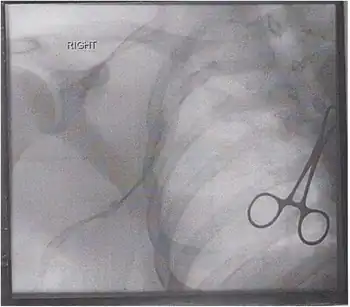

Duplex ultrasonography MR Venography

The traditional treatment for thrombosis is the same as for a lower extremity DVT, and involves systemic anticoagulation to prevent a pulmonary embolus.[10] Some have also recommended thrombolysis with catheter directed alteplase or mechanical thrombectomy with a large bore catheter and manual aspiration providing definitive intervention with an endovascular approach.[11] If there is thoracic outlet syndrome or other anatomical cause then surgery can be considered to correct the underlying defect.[12]